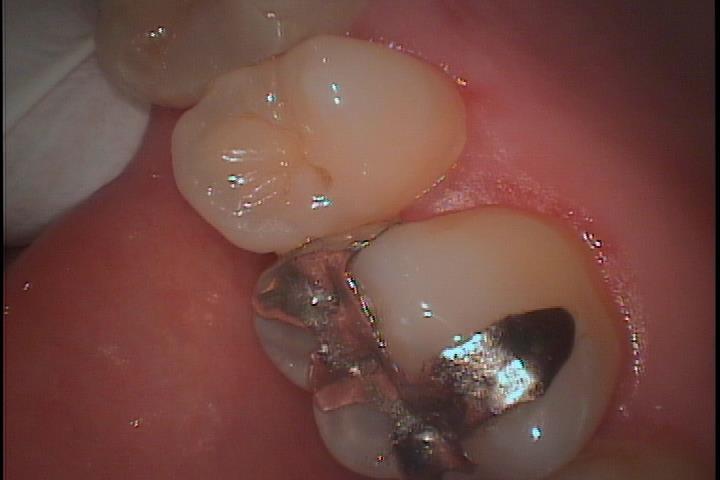

上顎右側第一大臼歯です。よく見るとメタルインレーと歯に境目があるのがわかります。一部黒くなって2次う蝕になっている様子も確認できます。

セメントが劣化すると境目から微小漏洩が発生し、2次虫歯が発生します。セメント劣化が少ないレジン系セメントの使用や、適合の良いマテリアルでセメントラインの少ないものを入れないといけません。